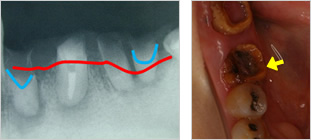

- 2位虫歯

- 虫歯が大きくなって、歯茎の下や骨のラインよりも深く虫歯になっている状態

- 治療しても長持ちしない

虫歯の箇所が大きいと削る量が増え、結果的に抜歯になってしまう。

赤い線が骨の位置

青い線が健康な歯の位置